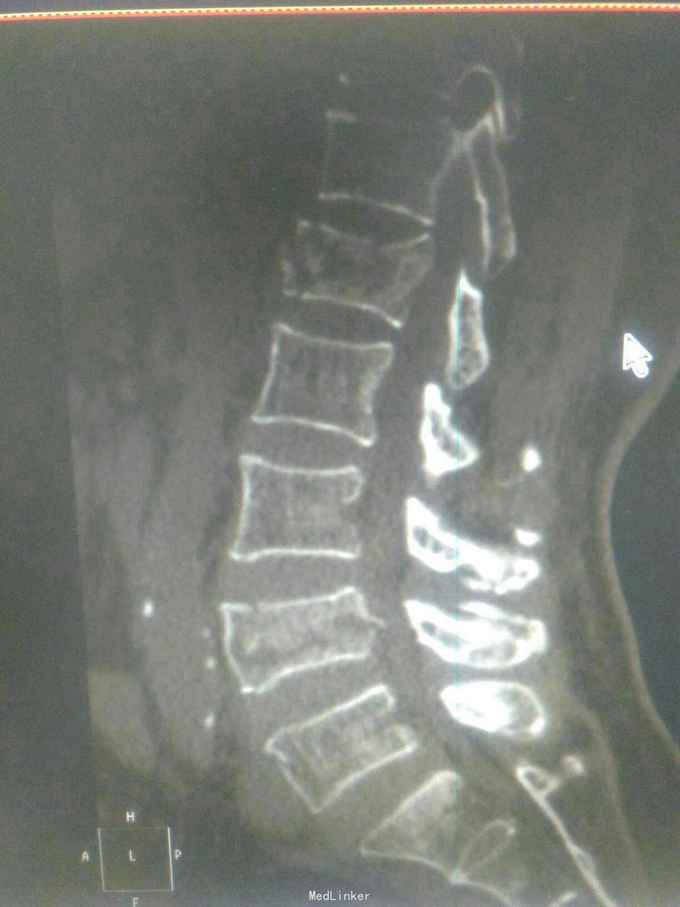

患者因高处坠落致腰痛部疼痛,双下会活动受限9小时入院。患者9小时前从3米高处坠落,腰骶部先着地,即时觉双下肢麻木,不能活动。

查体腰背部压痛,双下肢肌力0级,肌张力减低,会阴区,双下肢痛觉减低,触觉,精细觉正常,腱反射未引出,肛门反射消失,括约肌松弛。

诊断腰1,腰4椎体爆裂性骨折,腰5椎体压缩性骨折,脊髓圆锥损伤双下肢截瘫。患者入院后48小时内行了腰椎后路腰1.4椎体切开复位椎弓根钉内固定,腰1椎板切除,椎管扩大成形,横突间植骨融合术。